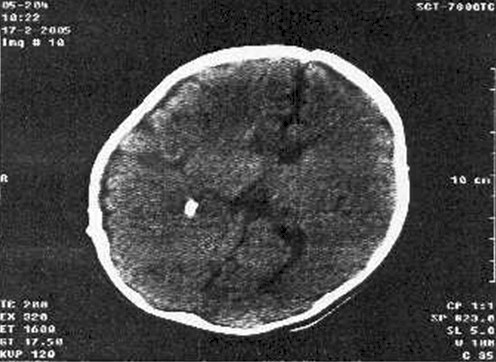

Imagen 2. Tomografía computarizada.

Incremento marcado del volumen de líquido cefalorraquídeo (LCR) y dilatación de cavidades ventriculares. Obsérvese la diástasis de suturas en lactantes con hidrocefalia.

La tomografía computarizada de urgencia coincidió con el resultado anterior y descartó signos de edema cerebral y lesiones con efecto de masa, observándose diástasis de suturas (imagen 2).

En nuestro caso se diagnosticó hidrocefalia aguda adquirida como complicación de una meningitis bacteriana en un paciente varón de 3 meses que una semana antes había sido admitido y tratado en la unidad de cuidados intensivos pediátricos de nuestro hospital como complicación de la sepsis, en presencia ahora de un cuadro de irritabilidad que alternaba con somnolencia, vómitos, fontanela anterior hipertensa y el aumento del perímetro cefálico. La ecografía cerebral reveló el marcado aumento de los diámetros de los ventrículos laterales en sus cuernos frontales, temporales y occipitales, lo que además aumentaba la relación ventrículo- hemisférica (Índice de Evans), por incremento del volumen de líquido cefalorraquídeo observado en la imagen 1, esta modalidad de neuroimagen es además la ideal para evaluar la presencia de ventriculitis por revelar los tabiques o bandas intraventriculares como complicación de ependimitis. La tomografía computarizada de cráneo (imagen 2) confirmó el diagnóstico ecográfico y descartó el edema cerebral y lesiones con efecto de masa, por ejemplo los abscesos yuxtadurales que por estar próximos a la convexidad no se visualizan bien por ecografía.